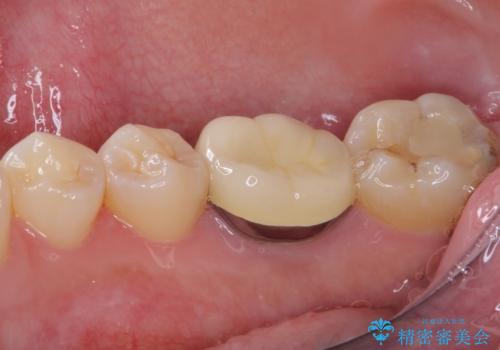

- 奥歯の歯肉から定期的に膿が出てくるとのことで来院された患者様です。

レントゲン写真などの診察を行った結果、根管治療が必要であったため、現在のクラウンを除去し、根管治療を行うこととしました。

根管治療後は症状を確認し、速やかにオールセラミッククラウンにて補綴治療を行うこととしました。